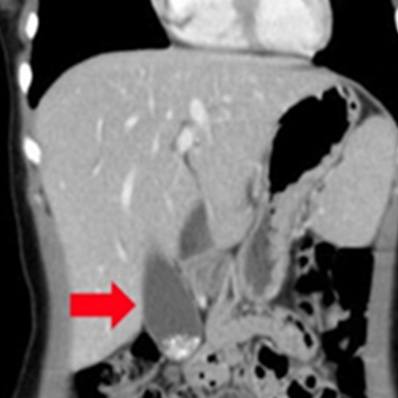

腹部大動脈瘤破裂